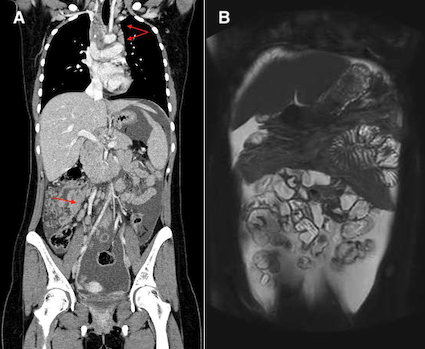

Gli esami ematochimici in corso di ricovero sono risultati nella norma, comprese le sierologie per le principali infezioni e i marcatori tumorali (salvo aumento di CA-125, 445 UI/ml); il Quantiferon è risultato positivo. Agli esami strumentali Rx torace negativa, mentre la TC torace evidenziava adenopatie mediastiniche e noduli polmonari apicali a sinistra (Figura 1); alla TC e RM addome multiple adenopatie e abbondante liquido ascitico (Figura 2), risultato poi negativo per bacillo di Koch (BK) su esame batterioscopico, colturale e analisi molecolare.

La PET-TC infine mostrava multiple adenopatie ipercaptanti di sospetta natura evolutiva, con riscontro alla biopsia di linfonodo laterocervicale di reazione granulomatosa con cellule epitelioidi e giganti multinucleate, senza necrosi, e ricerca di bacilli alcol-acido resistenti, ancora una volta negativa.

Veniva pertanto esclusa l’eziologia infettiva e ipotizzata una patologia tumorale. Il follow-up specifico è tuttavia risultato negativo, con riscontro alla laparoscopia esplorativa addominale di lesioni istologicamente negative per neoplasia ma evidenza di granulomi a cellule epitelioidi e giganti multinucleate a “corona di nuclei”, localmente necrotizzanti, compatibili con infezione da BK.